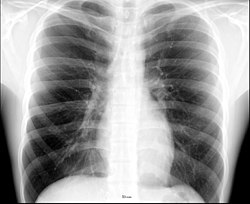

Рентгеноанатомия органов грудной клетки.

При изучении рентгеноанатомии органов грудной клетки обращают внимание на рентгеновскую структуру видимых костей и мягких тканей грудной клетки; форму и прозрачность для рентгеновских лучей областей, на которые проецируется лёгочная ткань (так называемых «лёгочных полей»), а также их структуру, сформированную тенями сосудов лёгких («лёгочный рисунок»); расположение и структурность корней лёгких; положение, форму куполов диафрагмы и синусов плевральных полостей; форму и размеры тени средостения (в том числе сердца).

Рентгеноанатомия лёгких в прямой проекции.

Лёгкие на рентгенограмме образуют лёгочные поля, располагающиеся по обе стороны от интенсивной тени средостения. Правое лёгочное поле короче и шире левого. В лёгочных полях различают верхушки (зоны выше ключиц), верхние отделы — от верхушек до передних отрезков вторых рёбер, средние отделы — между вторыми и четвёртыми парами рёбер, и нижние отделы — от четвёртых рёбер до диафрагмы. Лёгочные поля в норме очень светлые (тёмные на негативе) из-за высокой рентгенопроницаемости заполненной воздухом лёгочной ткани. Структура лёгочных полей называется лёгочным рисунком, анатомическим субстратом которого являются лёгочные сосуды и, в малой степени, лёгочный интерстиций. Лёгочный рисунок визуализируется в виде переплетения сосудистых теней тяжистого, округлого и овального вида, более интенсивных в местах их пересечений. В направлении от корней лёгких к периферии рисунок лёгочных сосудов становится беднее и совсем не визуализируется на расстоянии 1—1,5 см от края лёгочных полей. Лёгочный рисунок наиболее густой в нижних отделах лёгочных полей, обедняясь к верхушкам. Тени бронхов на рентгенограмме визуализируется в виде двойных полосок или колец с просветлением внутри.[3][4]